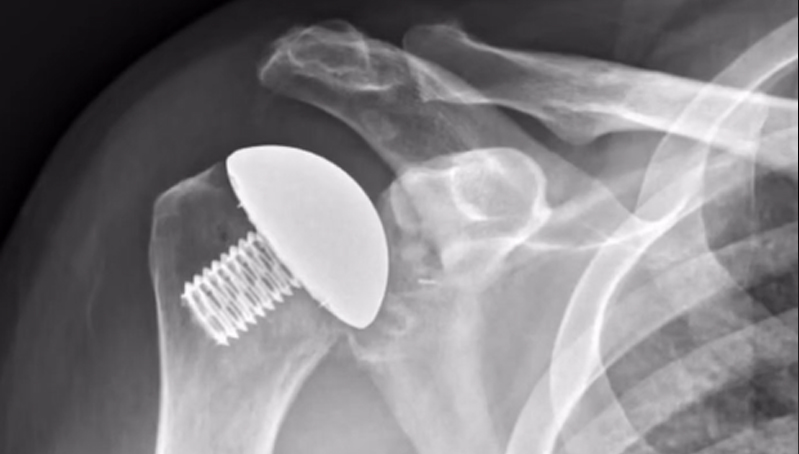

Two types of total

shoulder replacements:

Anatomic and Reverse. The shoulder is a ball and socket joint. The ball portion

Exactech Should Replacement option

Replacement option from Orthopedic Group

Exactech Should Replacement

It helps the surgeon decide where to remove the bone and place the shoulder implant.